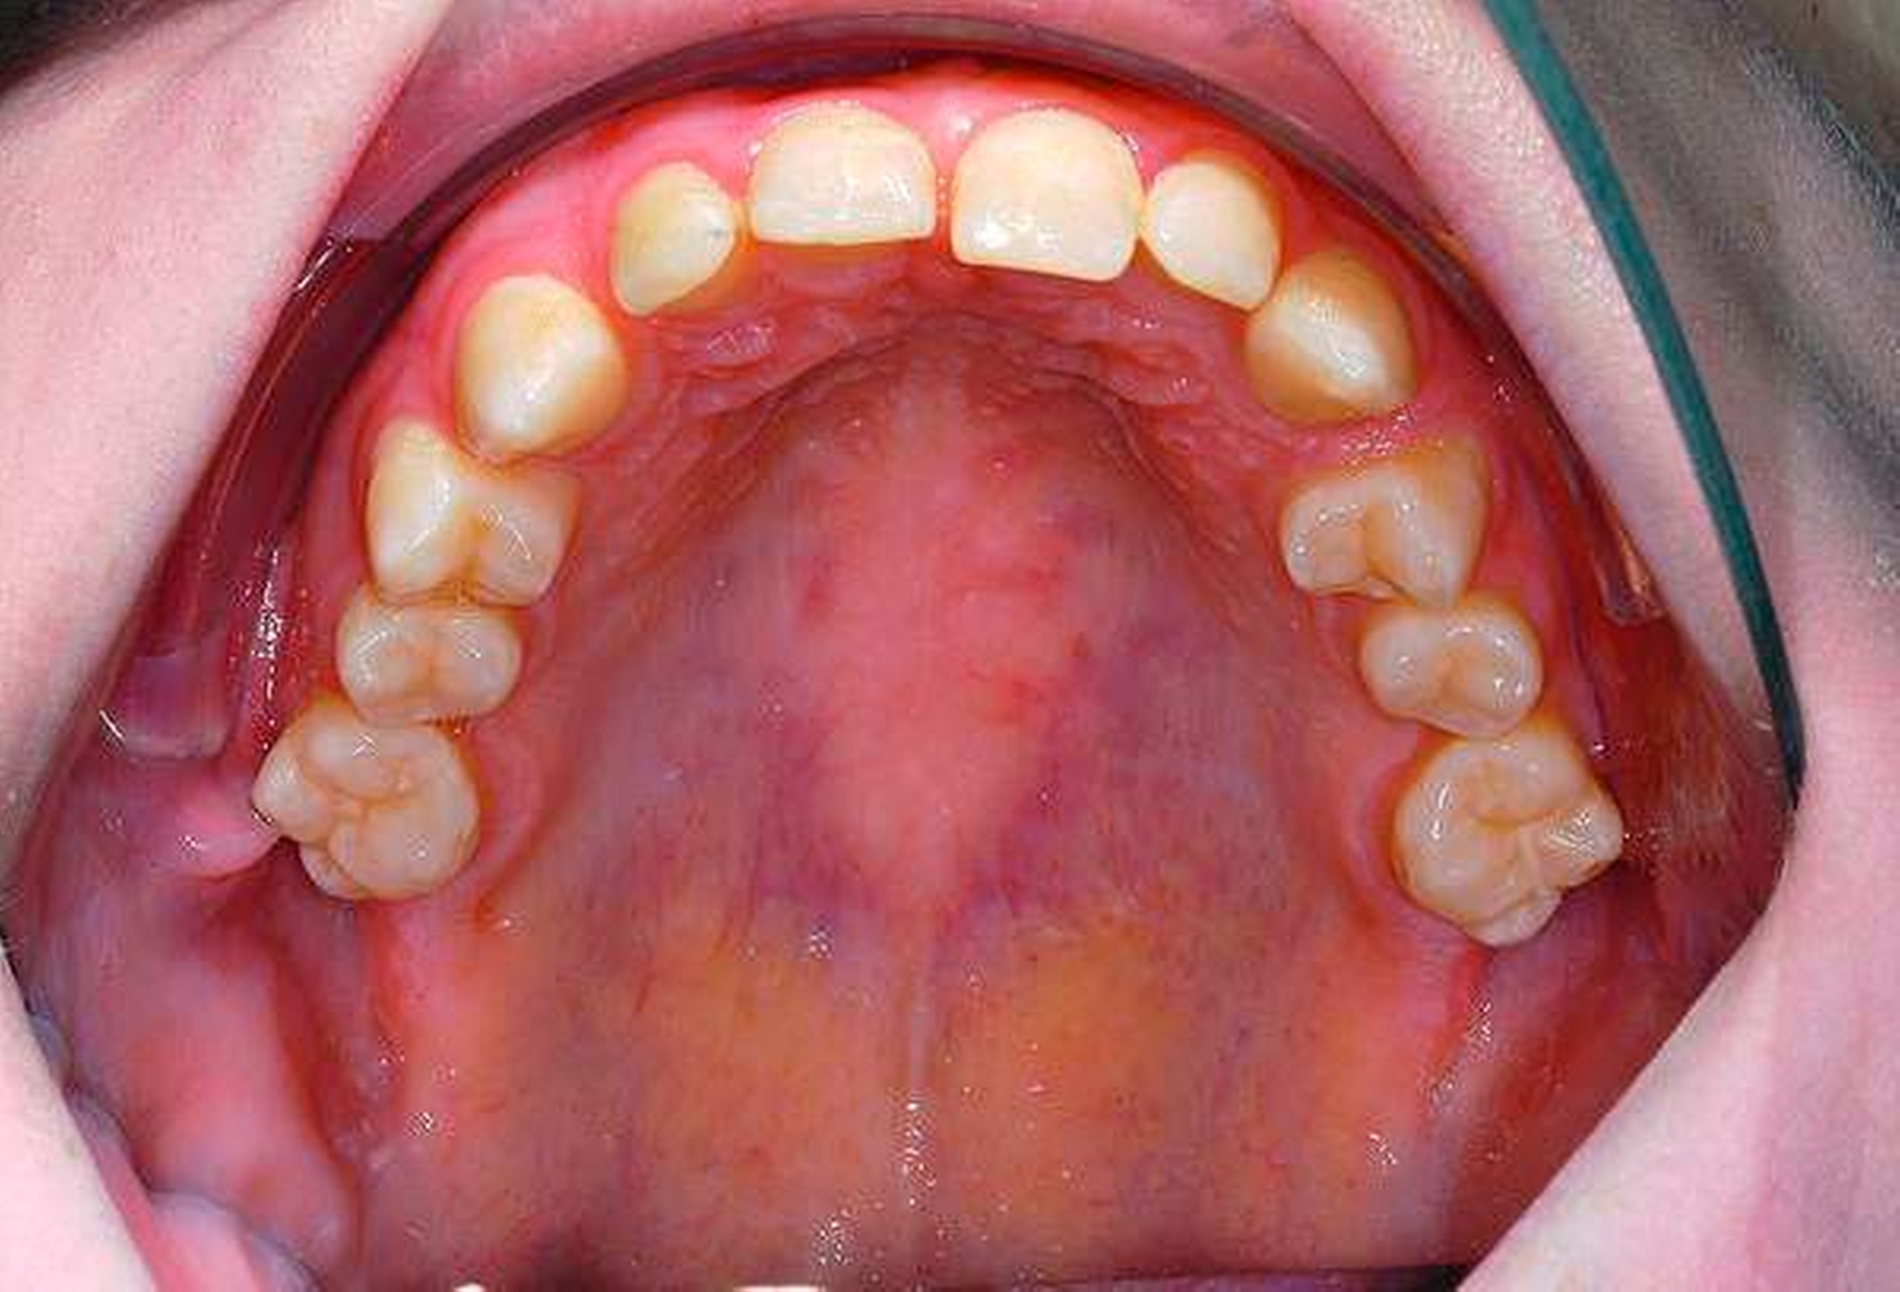

Eine 20-jährige Patientin wurde durch ihren Hauszahnarzt an unsere Poliklinik zur Entfernung aller Weisheitszähne überwiesen (Abbildung 1). Der Hauszahnarzt habe vergeblich versucht, diese zu extrahieren, die Lokalanästhesie habe keine ausreichende Wirkung erzielt.

Die Entfernung aller Weisheitszähne wurde schließlich nach einem weiteren frustranen Extraktionsversuch unter Lokalanästhesie in Intubationsnarkose durchgeführt, der postoperative Verlauf gestaltete sich komplikationslos, auffällige Blutungen traten nicht auf (Abbildungen 2 und 3).